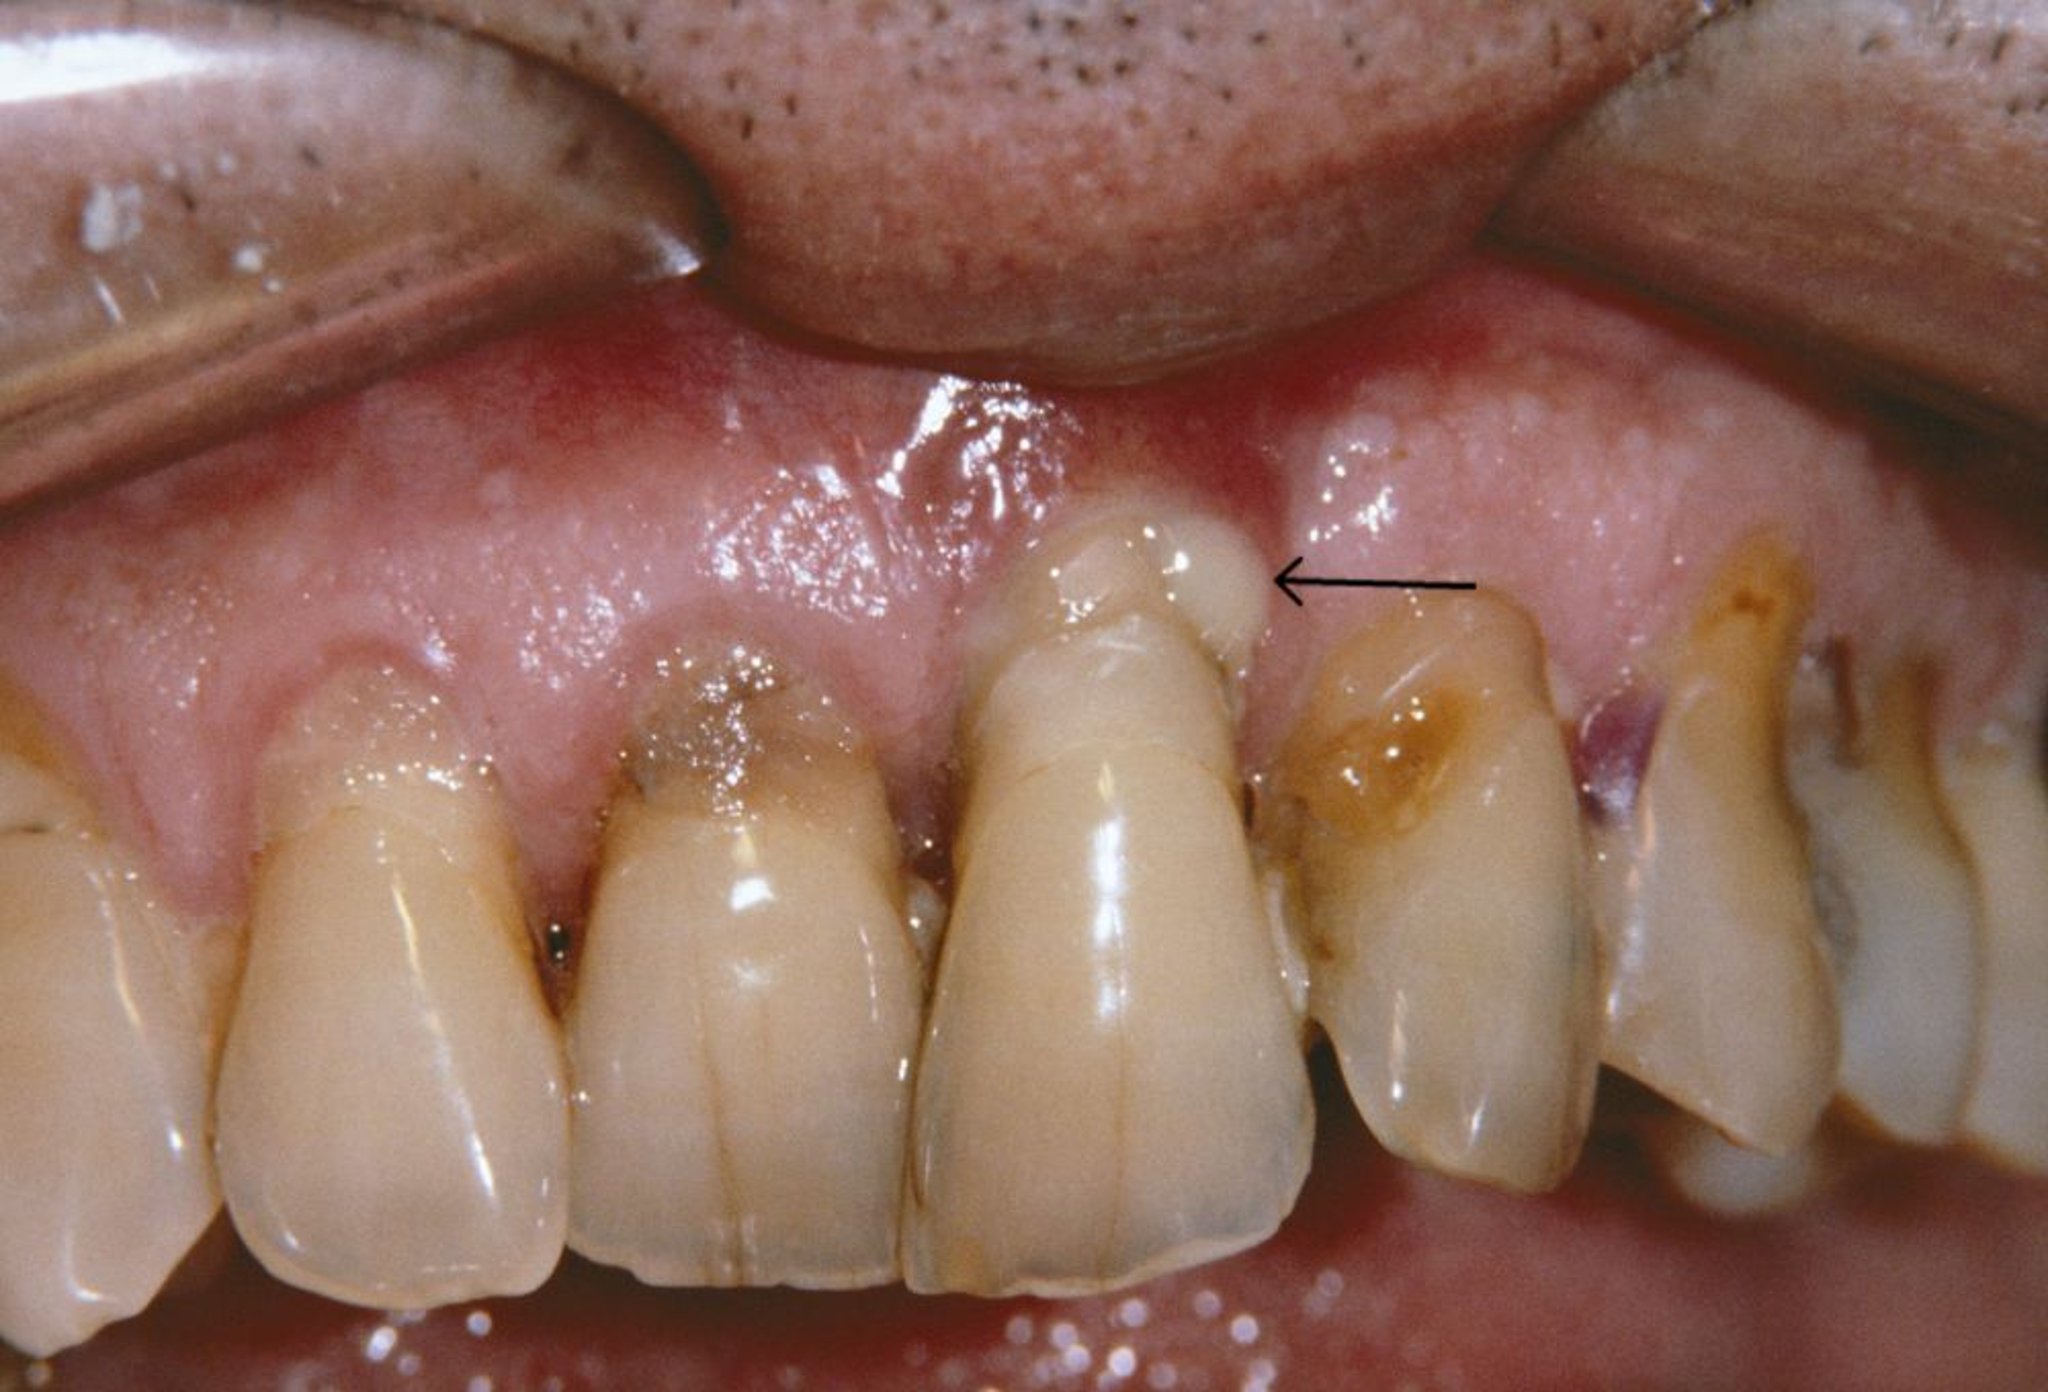

Dieses Foto zeigt einen Zahnfleischrückgang und einen periodontalen Abszess (Pfeil) bei einem Patienten mit Parodontitis.